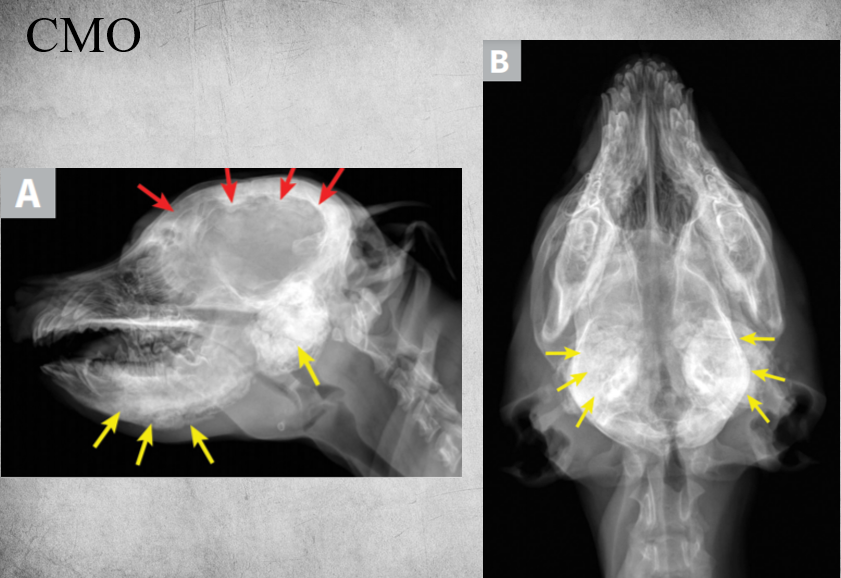

“CMO”

Is a non-neoplastic proliferative bone disease (the new growth grows outward typically).

Usually 3-8 mo old dogs affected

- Especially West Highland white terrier – autosomal recessive.

- Cairn terrier, Scottish terrier

Marked new bone formation in:

- Mandibulae

- Bullae

- In some cases, also the cranium and frontal bone.

Great variability in presentation – bilateral, unilateral, different areas can be affected

Self-limiting disease! changes may even disappear in time